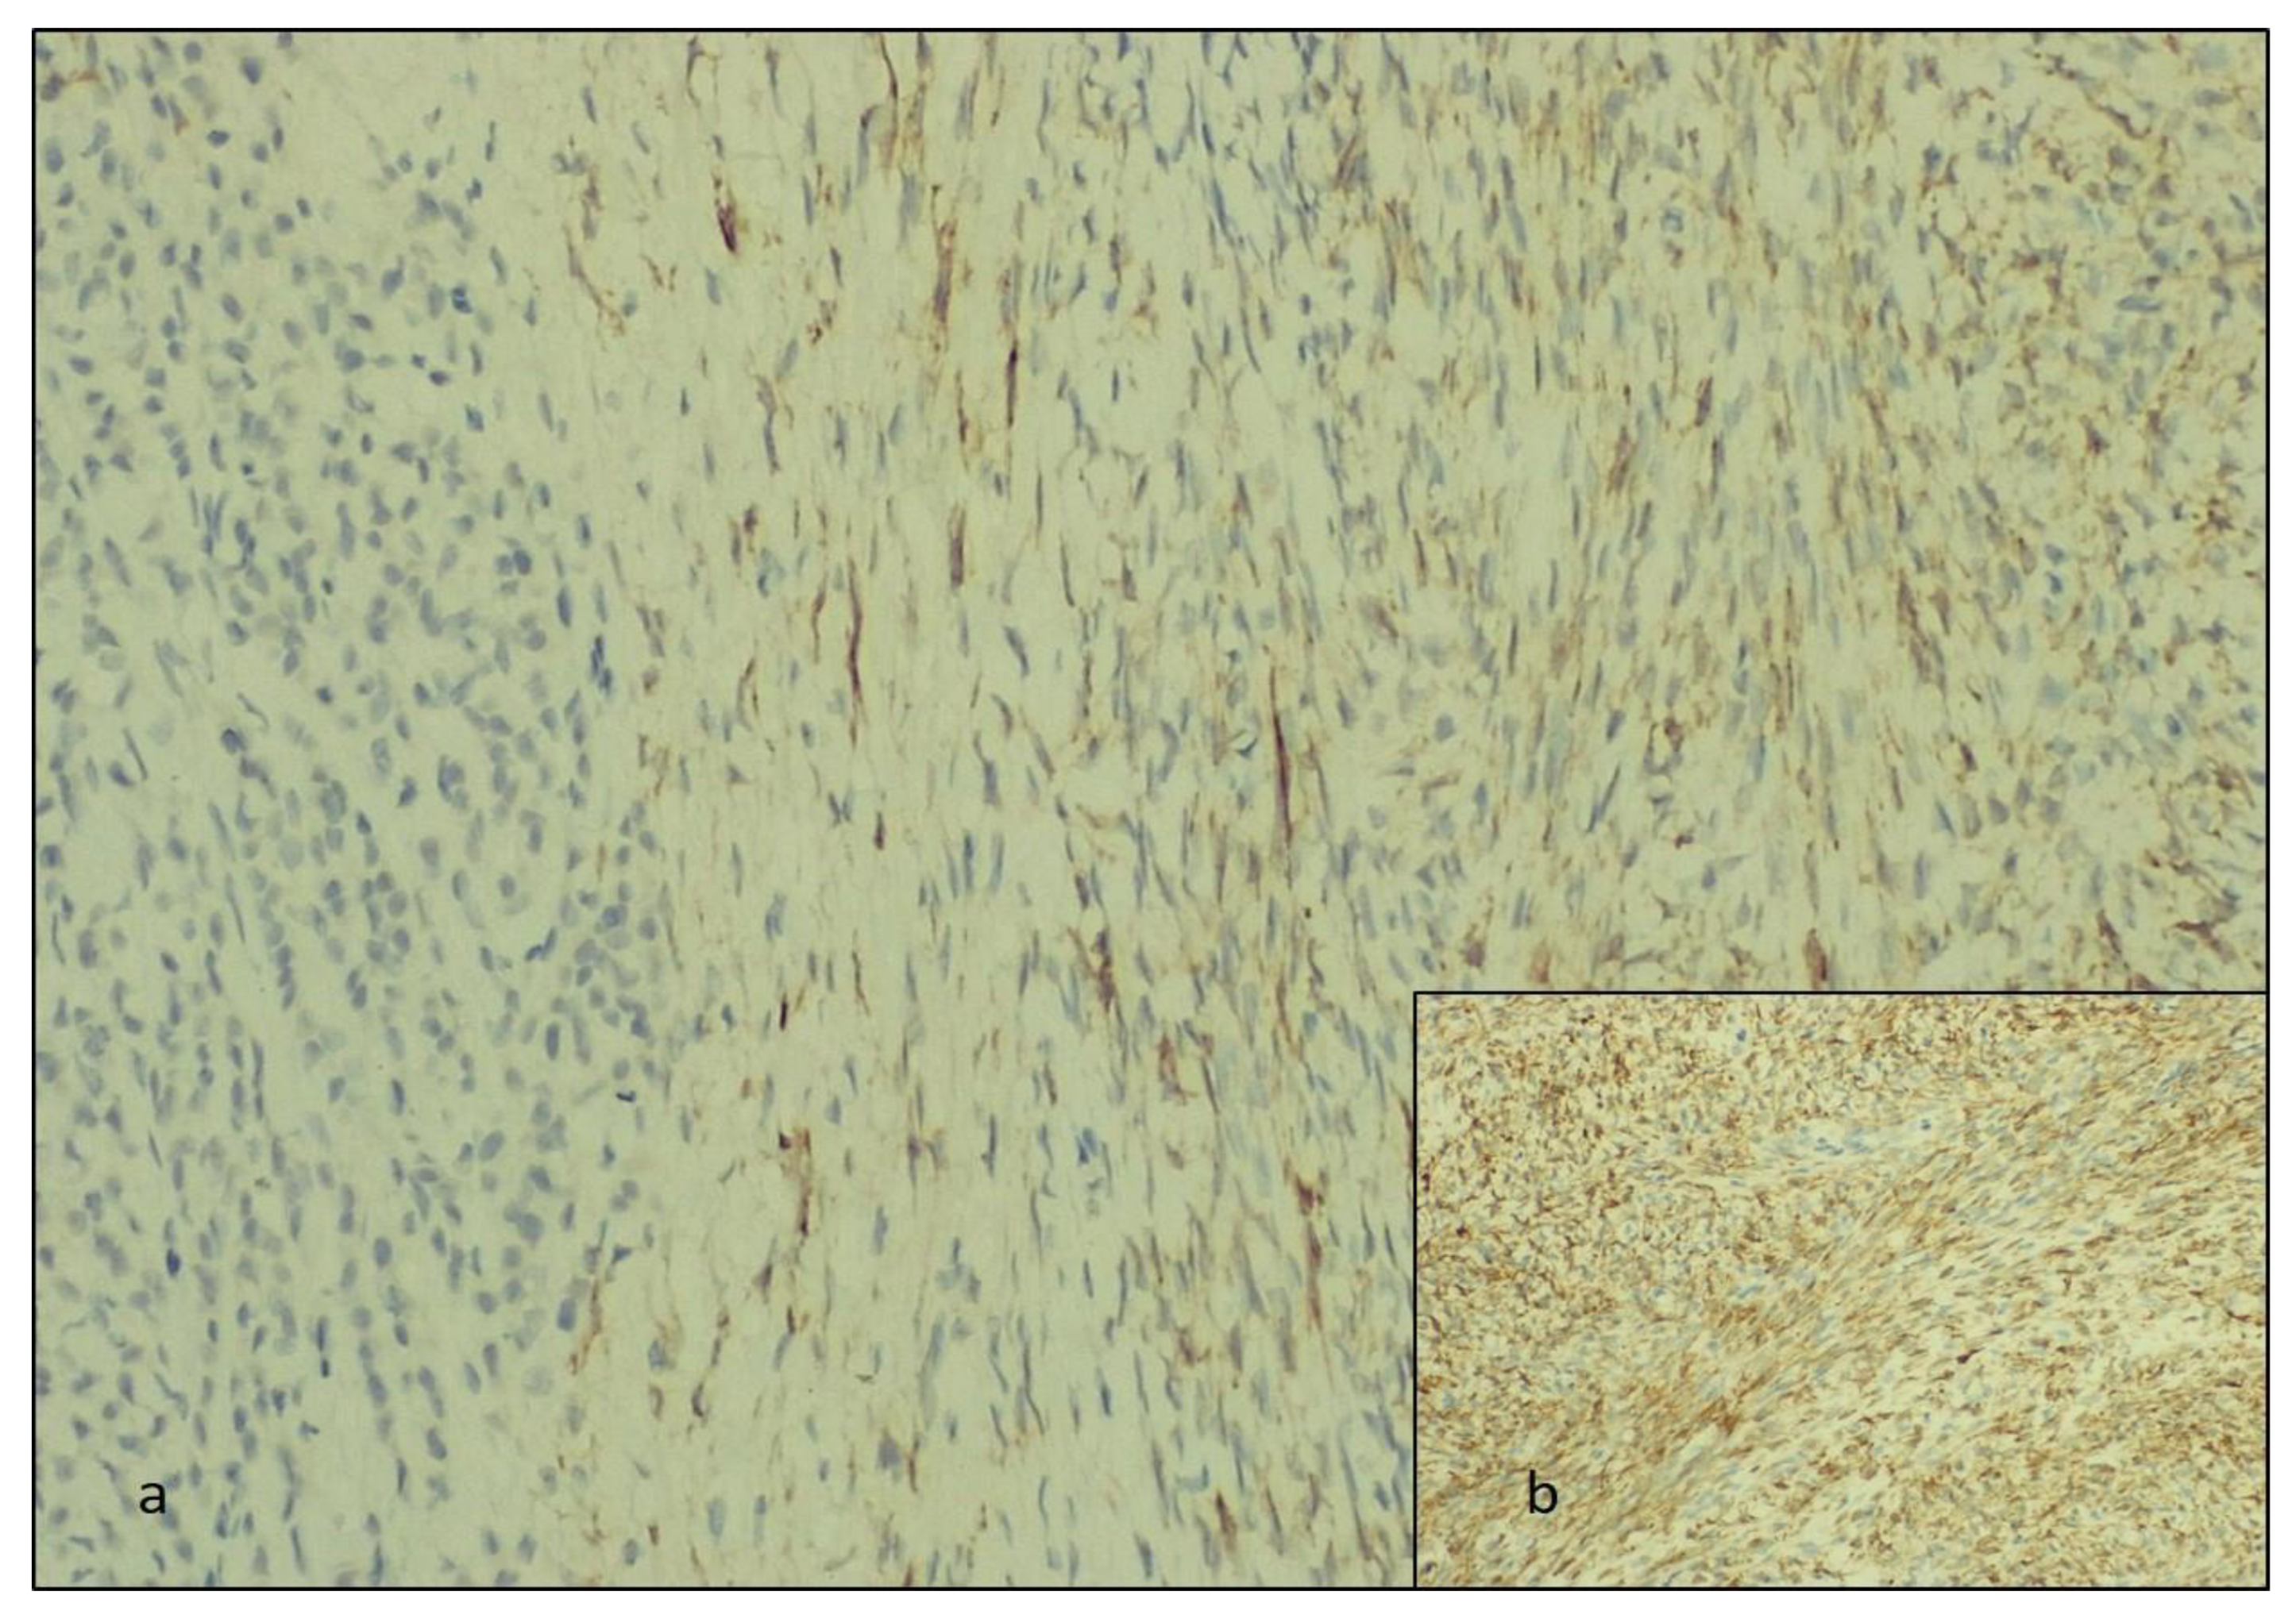

Gross and Microscopic Evaluation